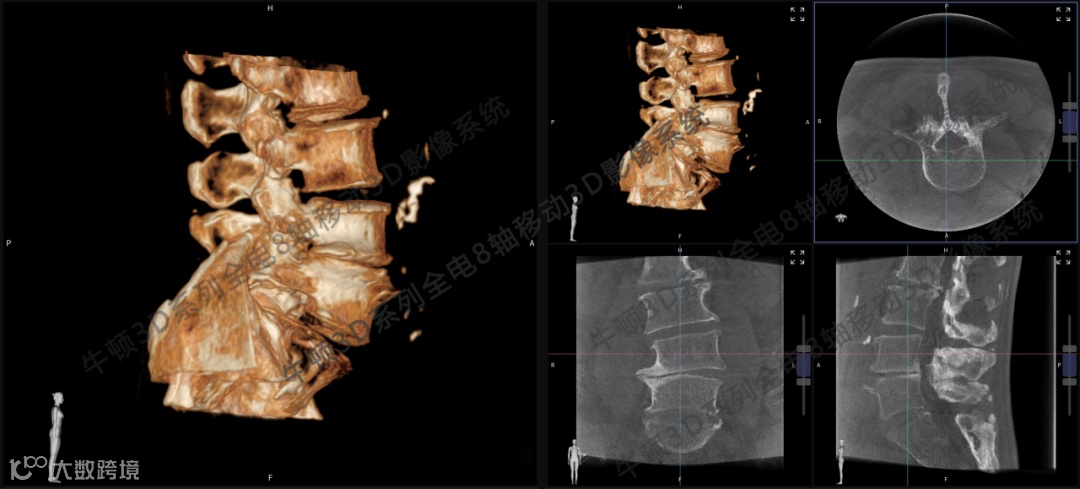

三维影像案例2:清晰的三维立体成像及切片图像,让医生准确判断腰椎骨病患者脊柱的稳定性、组织结构病变程度、椎管受压等病情细节,从而制定更有针对性的治疗方案。